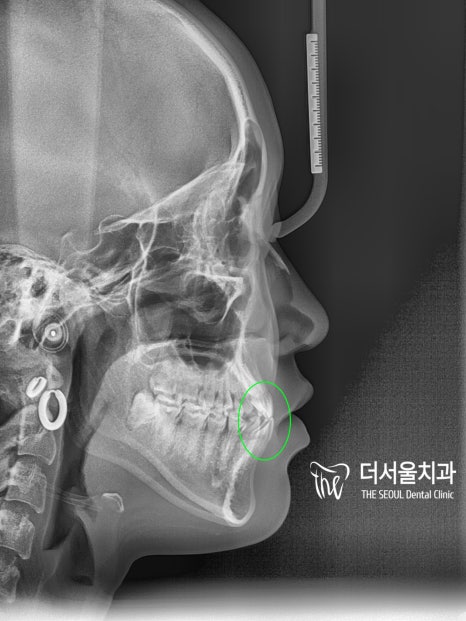

측면 ceph을 비교해 보면

입술의 긴장감이 사라져

자연스러운 모습으로 바뀌었습니다.